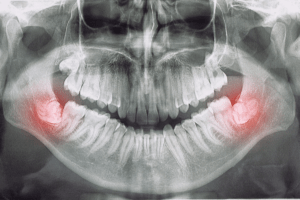

Qué dice el color de las encías sobre tu salud bucodental

El color de las encías puede darnos pistas sobre cómo se encuentra nuestra salud oral y general. Descubre qué significa cada uno y evita problemas graves. La salud bucodental está estrechamente relacionada